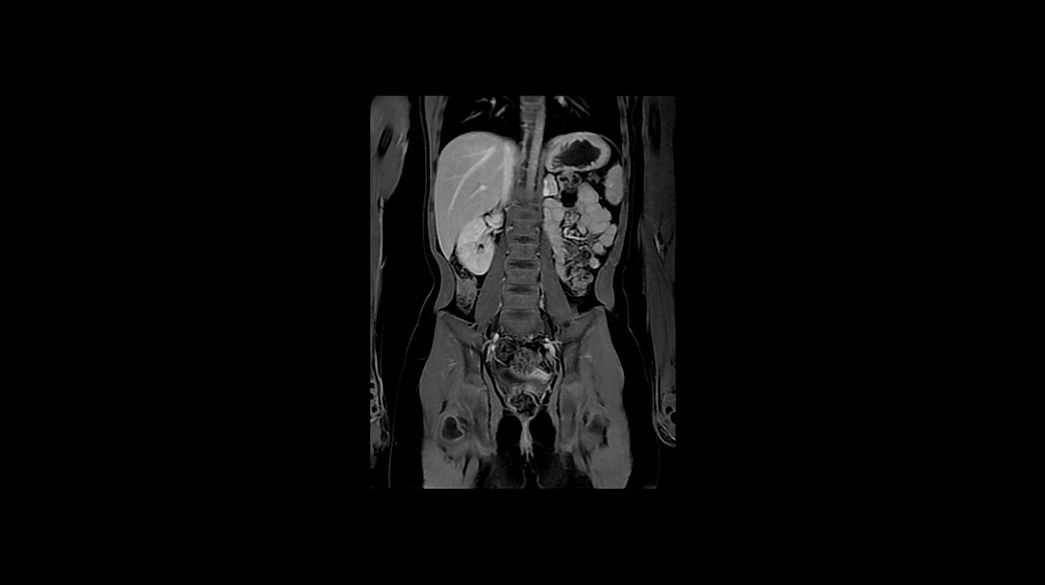

Pediatric MRI imaging applications

Precision and personalization